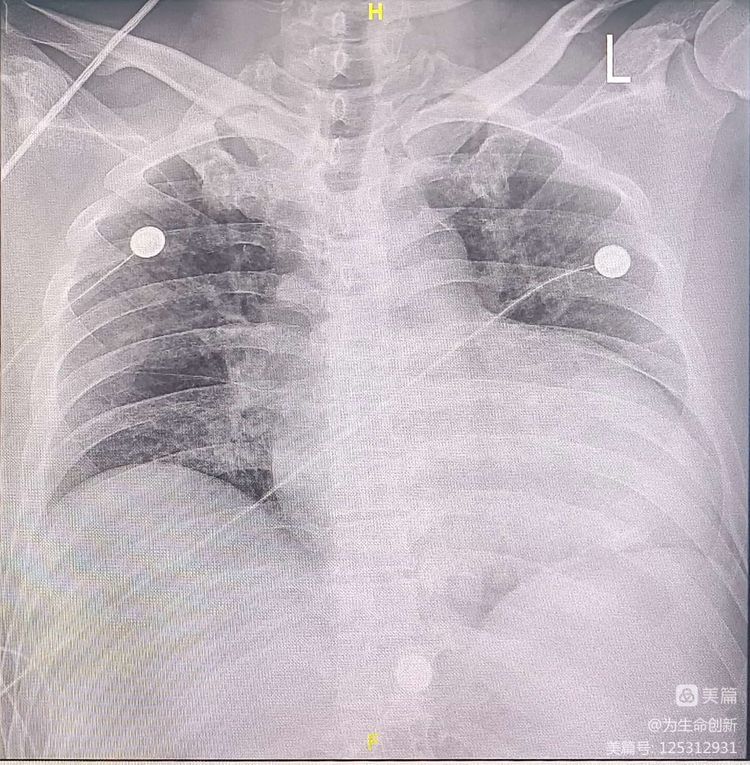

患者肖某,男,53岁,BMI:27,因反复气促2年余,20余天前行走过程中突感心慌头晕,数秒后晕厥倒地,持续半分钟后苏醒。近期又自觉心慌胸闷,现为求进一步治疗就诊于云南阜外心血管病医院。完善超声、动态心电图及DX光片提示:心脏扩大,EF值:21%,短阵室速。术前诊断:晕厥史,扩张型心肌病,阵发性AF,VT,NYHA II级。

术后影像:电极贴靠良好